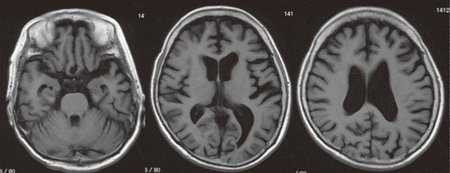

この型の認知症の症状の出現は、脳の中でも、近時記憶を司る海馬や人間らしさを司り大脳の表面をおおっている大脳皮質といわれる部分の萎縮が徐々に進行し、脳全体の機能が衰えていくことに端を発します。そして、記憶に関係するアセチルコリンという神経伝達物質が減少していることが分かっています。

アルツハイマー型認知症の人の脳ではアミロイド仮説といわれている老人斑と神経原線維変化が特徴的病理所見です。灰白質にも白質にも萎縮や変性がみられます。